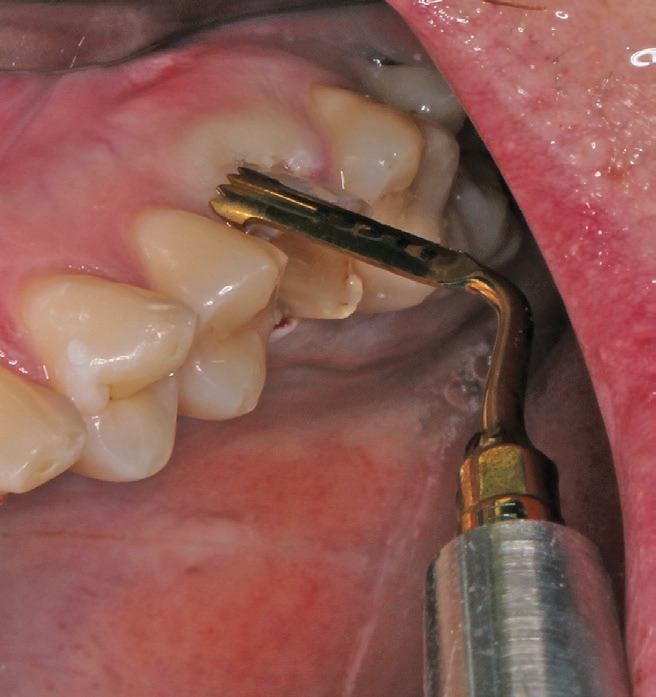

Die Operation erfolgte in Lokalanästhesie (Ultracain® D/S forte, Aventis, Frankfurt) in Form einer Infiltrationsanästhesie bukkal und palatinal der Region 26. Mittels der Instrumentenspitze EXP4-L (Piezosurgery, Mectron, I-Genua) wurden die dentogingivalen Fasern vorsichtig durchtrennt und der Desmodontalspalt geweitet (Abb. 5 und 6). Nach Durchtrennung der Wurzeln wurde der Zahn mit einer Extraktionszange aus dem gelockerten Zahnfach vollständig entfernt (Abb. 7 und 8).